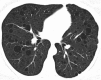

Hamartomas are tumours composed of mesenchymal tissues such as cartilage, fat, connective tissue and smooth muscle and can be found in virtually any organ system. These masses commonly develop sporadically, but are also seen in certain syndromes such as tuberous sclerosis or Carney triad. While their imaging appearance varies depending on the organ they arise from, findings are usually unique and a diagnosis can be confidently made. Radiologists must be aware of the clinical and imaging presentations of these lesions with the particular goal of avoiding unnecessary studies or invasive procedures. Furthermore, knowledge of common syndromic entities is crucial, as the radiologist may be the first to suggest the diagnosis.